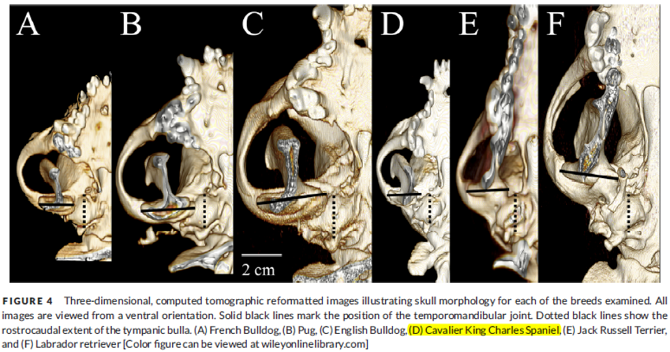

The tympanic cavity (also called the middle ear cavity) is a rounded, hollow space behind the eardrum, (tympanic membrane) which is encased in the tympanic bulla, a thin, bubble-like bony vessel. It is within this cavity that the PSOM mucus is located. (See the "middle ear cavity" in the diagram above.) In cavaliers, this cavity has been found to be much smaller and flatter than the large, rounded cavity in other breeds.

In a March 2006 article, the radiologists authors noted that, while the canine "tympanic cavity is usually quite large and rounded", in the cavalier, "it is smaller and flatter." Similarly, in a July 2017 article, a team of UK researchers used computed tomography (CT) to study the tympanic bullae of four brachycephalic breeds (pug, French bulldog, English bulldog, and cavalier) and compared them to two control breeds (Labrador retriever and Jack Russell terrier). They found that the CKCS had significantly flatter tympanic bullae than the other brachy breeds. (See Figure 4, below, of the July 2017 article's comparisons of the tympanic cavities of the cavalier and the five other breeds.) They also found middle ear effusion material in 68% of the cavaliers. They speculated that the flatter shape of the CKCS tympanic bulla may explain the reason for such a high incidence of PSOM in the breed. The authors stated:

"Cavalier King Charles Spaniels have been described to have a unique disease resulting in the formation of a buildup of highly viscous mucus within the middle ear (primary secretory otitis media or otitis media with effusion) of dogs without clinical evidence of otitis externa. ... The finding of an anatomical variation in the shape of the tympanic bulla of Cavalier King Charles Spaniels may offer a potential explanation for the pathogenesis of this disease in addition to the previously suggested changes in the orientation and function of the auditory tube. However, given the lack of histopathology and contrast-enhanced CT scan evaluations in the current study, this hypothesis is speculative. Further investigation to identify potential pathway alteration of the auditory tube in the Cavalier King Charles Spaniel would be an interesting addition for further clarification of this disease process."

In a

July 2017 article, a team of UK researchers (Ben Mielke, Richard

Lam, Gert ter Haar [right]) studied the tympanic bullae of four brachycephalic

breeds (pug, French bulldog, English bulldog, and cavalier King Charles

spaniel -- 25 dogs of each breed) and compared them to two control

breeds (Labrador retriever and Jack Russell terrier). They found that

the CKCS had significantly flatter tympanic bullae than the other brachy

breeds. (See the article's Figure 4, below.) They also found middle ear effusion material in 68% of the

cavaliers. They speculated that the flatter shape of the CKCS tympanic

bulla may explain the reason for such a high incidence of PSOM in the

breed. The authors stated:

In a

July 2017 article, a team of UK researchers (Ben Mielke, Richard

Lam, Gert ter Haar [right]) studied the tympanic bullae of four brachycephalic

breeds (pug, French bulldog, English bulldog, and cavalier King Charles

spaniel -- 25 dogs of each breed) and compared them to two control

breeds (Labrador retriever and Jack Russell terrier). They found that

the CKCS had significantly flatter tympanic bullae than the other brachy

breeds. (See the article's Figure 4, below.) They also found middle ear effusion material in 68% of the

cavaliers. They speculated that the flatter shape of the CKCS tympanic

bulla may explain the reason for such a high incidence of PSOM in the

breed. The authors stated:

"Cavalier King Charles Spaniels have been described to have a unique disease resulting in the formation of a buildup of highly viscous mucus within the middle ear (primary secretory otitis media or otitis media with effusion) of dogs without clinical evidence of otitis externa. ... The finding of an anatomical variation in the shape of the tympanic bulla of Cavalier King Charles Spaniels may offer a potential explanation for the pathogenesis of this disease in addition to the previously suggested changes in the orientation and function of the auditory tube. However, given the lack of histopathology and contrast-enhanced CT scan evaluations in the current study, this hypothesis is speculative. Further investigation to identify potential pathway alteration of the auditory tube in the Cavalier King Charles Spaniel would be an interesting addition for further clarification of this disease process."